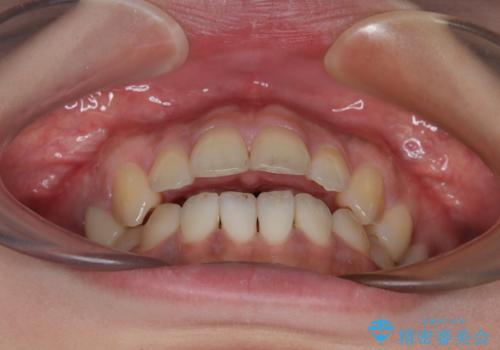

開咬をワイヤー装置で矯正治療

- 上下前歯が非接触となっている咬み合わせを気にして来院された患者様です。

開咬となっている原因の大半は、舌の突出癖によるものであるため、治療開始前から舌のトレーニングを開始し、スムーズに治療が進むようにしました。

開咬の方は、インビザライン矯正治療が適していますが、自己管理の煩わしさと、転勤の可能性がありマウスピース矯正であると通院しなくなるだろうとのことで、ワイヤー装置にて矯正治療を行うこととしました。